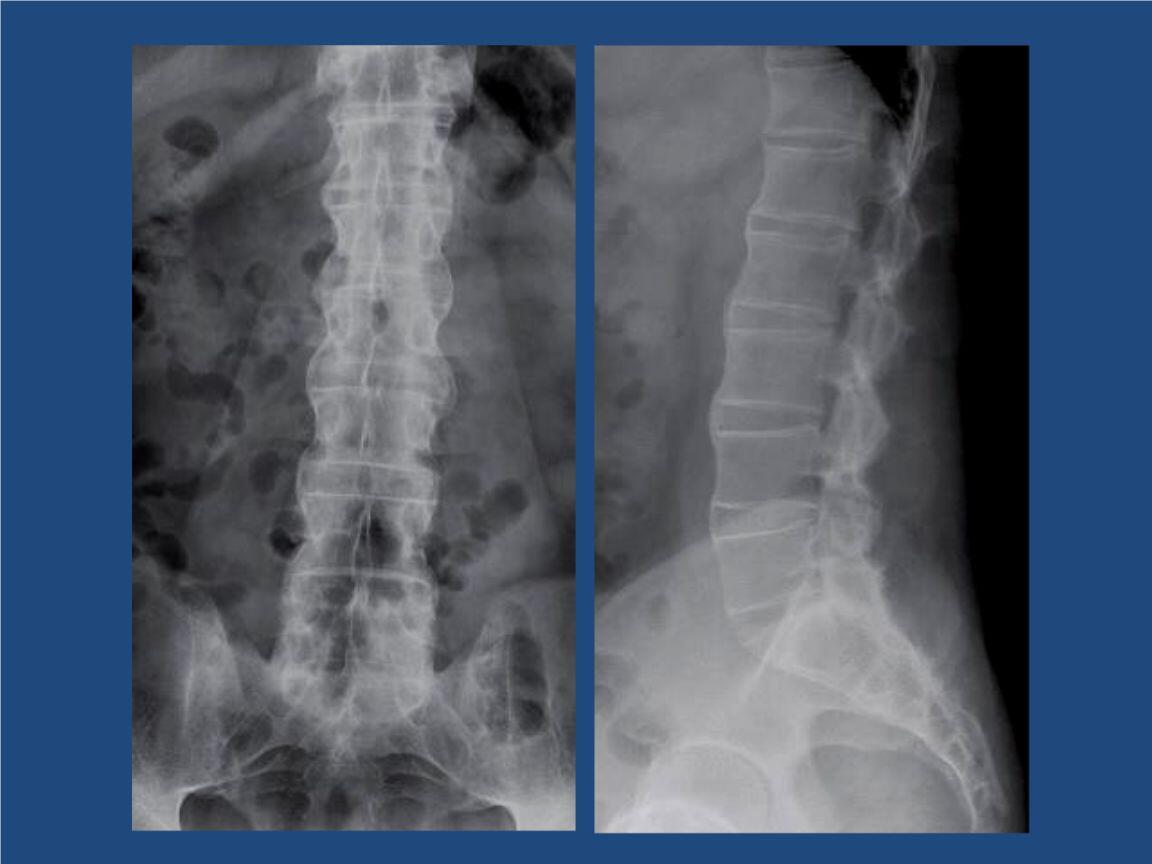

以15-30岁的中青年男性为主。该病缓慢,间歇性疼痛,多个关节受感染。脊髓活动受限,关节异常。x线检查显示骶髂关节和钙化的脊柱韧带之间的空间很窄,通常类似竹节。